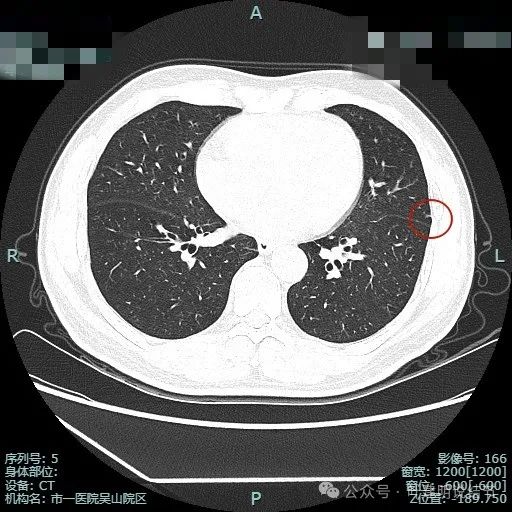

病灶7:左上叶胸膜下微小不足1毫米点状高密度,无法定性,但良性可能性大,因为密度显得较高;

病灶8:距离胸膜约1.5厘米许微小磨玻璃结节,大概1-2毫米之间,轮廓较清,以肺泡上皮增生可能性较大;

病灶9:左上叶胸膜下微小结节,密度不如病灶7高,又不如病灶8大,无法确定性质,但必能随访。

病灶13:左上叶舌段磨玻璃结节,但呈长条状,贴着胸膜,纤维条索可能性稍大,但由于密度不够高,也无法完全除外肿瘤范畴的肺泡上皮增生或不典型增生,但必能随访。

病灶14:左上叶微小结节,密度较高,但未钙化,考虑增殖灶可能性大。